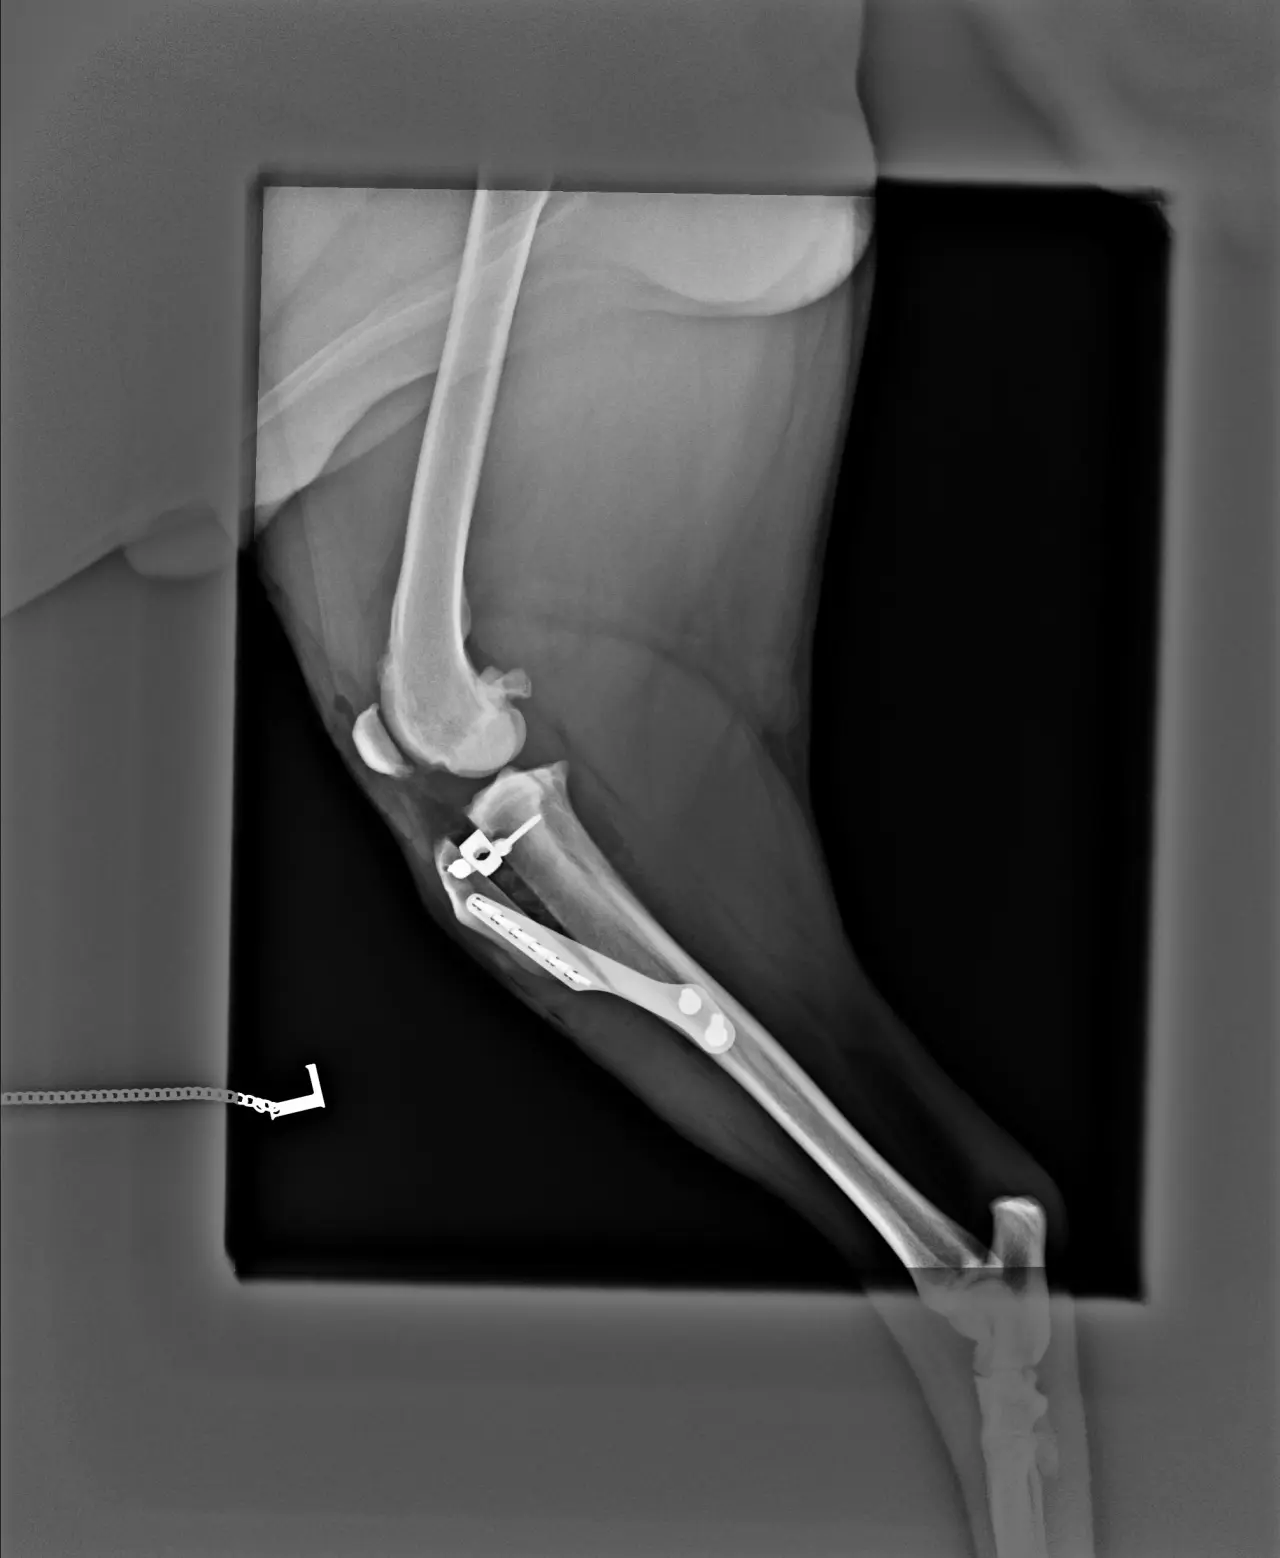

Pokud nevíte, jak taková operace probíhá, je to nepříjemná záležitost, kterou by jistě nikdo z nás nechtěl zažít. Jedná se o rozříznutí kosti a voperování titanové vložky a kostního štěpu pro stabilizaci kosti v nové poloze (řekněme to trochu laicky). Pro představu zde je pooperační RTG snímek.